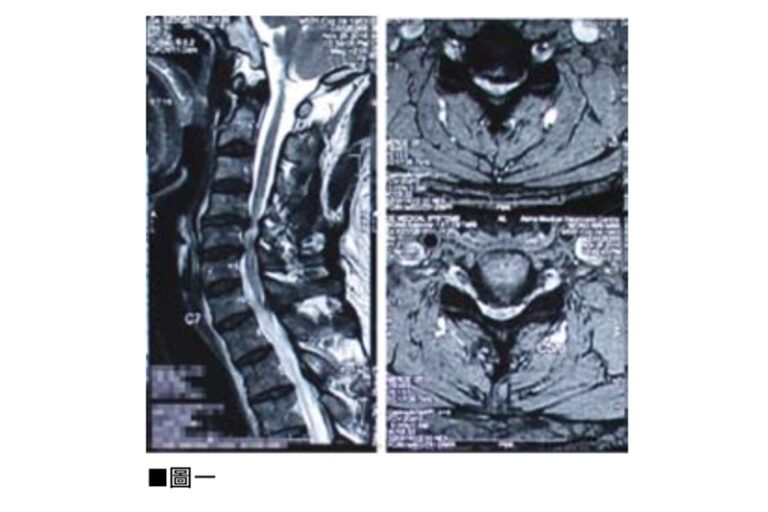

頸椎前路椎間盤切除及椎體融合手術(Anterior Cervical Discectomy and Fusion,ACDF)是以外科手術來治療頸椎的病變問題。導致頸椎病變多是因退化性、勞損性或意外受傷造成。病變會發生在頸椎間盤、頸椎的小面關節,或是頸椎體骨。由於頸椎中央包含了負責控制我們四肢、軀幹及大小便的中樞神經,所以頸椎病人除了有頸椎不穩定的症狀外,亦會有神經受壓的病徵。頸椎不穩定會引起肌肉繃緊、頸背痛、膊頭痛及頭痛。而神經受壓會令感官神經及運動神經功能失調,病人會有手腳神經麻木痺痛、肌肉無力、平衡失調、行路不穩、小便頻密、夜尿及便秘情況。此外反射神經及交感迷走神經的功能失調,亦會導致病人頭暈、耳鳴、腸胃不適甚至情緒不穩定。